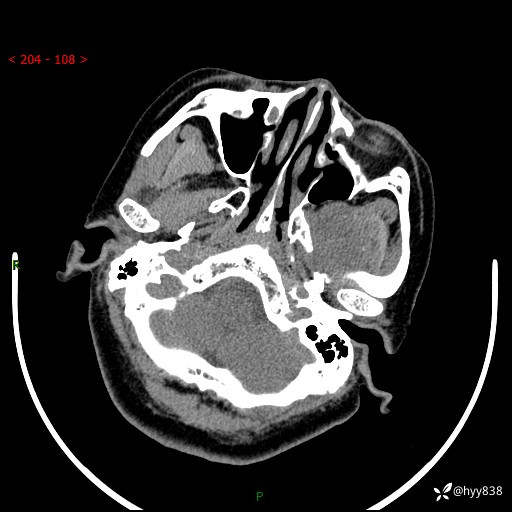

颅脑CT平扫